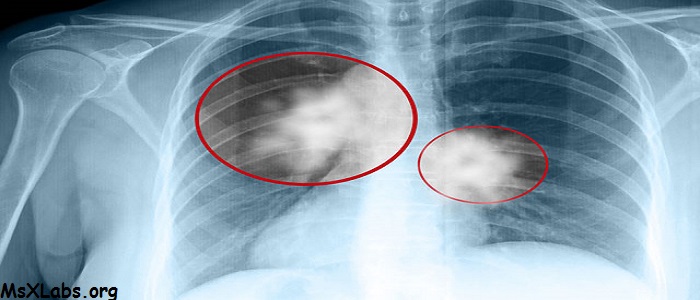

Akciğer kanseri belirtileri nasıl olur. Akciğer kanseri nasıl olur belirtileri. Akciğer kanserinin belirtileri neler akciğer kanseri neden olur tedavisi ailesinde akciğer kanseri olanlar için risk artıyor. Akciğer kanseri tüm kanser ölümlerinin erkek ve kadında en sık nedenidir. İyileşmeyen öksürük az miktarda olsa kanlı ösürük nefes darlığı göğüs ağrısı ses kısıklığı i̇stemsiz kilo kaybı kemik ağrısı baş ağrısı.

Akciğer kanseri belirtileri nelerdir. Dünyada her yıl yaklaşık 1 3 milyon kişi akciğer kanseri sebebiyle ölmektedir. Ancak hızlı ve ağrılı gerçekleşmesi akciğer kanseri belirtileri arasında yer alıyor. Sigarayı bırakarak uzun yıllardır sigara içmiş olsanız bile akciğer kanserini geliştirme olasılığını önemli ölçüde azaltabilirsiniz.